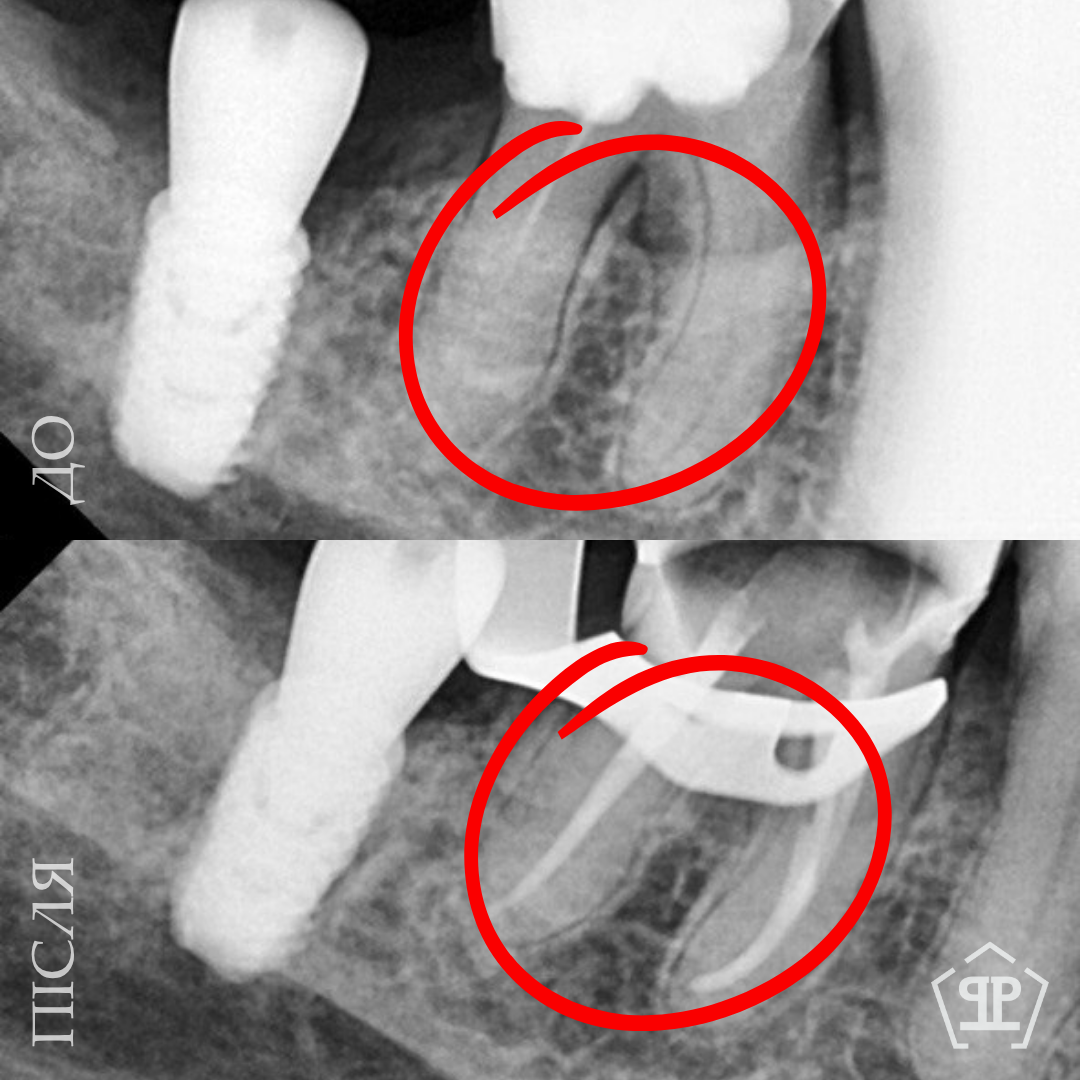

Во время диагностики обнаружен отлом фрагмента инструмента в корневом канале. Выполнено его безопасное извлечение, повторное перелечивание каналов, очистку и герметичное пломбирование.

Перелечивание с удалением двух переломанных инструментов. Пациент обратился с осложнением предварительного эндодонтического лечения. В каналах были обнаружены два переломанных инструмента. Выполнены их удаление и пломбирование каналов с соблюдением современных эндодонтических протоколов.